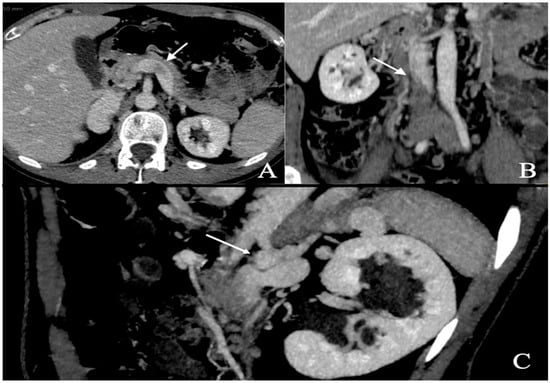

A respiratory alkalosis was found at the blood gas analysis so in suspicion of PE, Computed Tomography Angiography (CTA) was performed and did not detect any sign of pulmonary thromboembolism but azygos and hemiazygos vein dilatation (Figure 1) and a congenital abnormality of the IVC, in addition to DVT of iliaco-femoral veins with involvement of the IVC, renal veins, and mesenteric vein (Figure 2). Anticoagulation with low molecular weight heparin (LMWH) 1 mg/kg every 12 h subcutaneously was started.

Figure 2.

Abdominal angio-TC: extensive deep thrombosis involving femoral and iliac veins, renal veins (A—white arrow), IVC (B—white arrow), inferior mesenteric vein; abnormal hemiazygos and lumbar vein dilatation (C—white arrow).